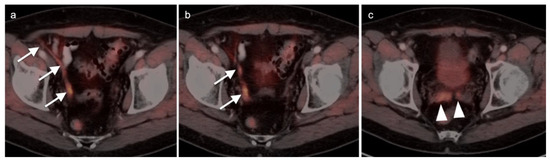

2.2. Ovarian Epithelial, Fallopian Tube and Primary Peritoneal Carcinoma